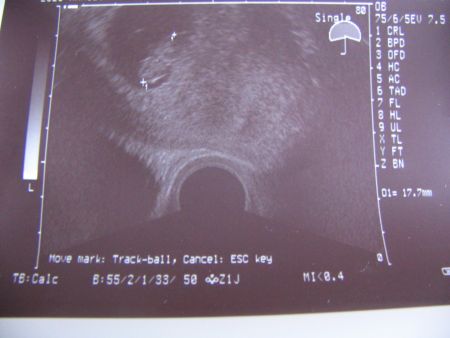

Íme Kistöki első képe:

Kép